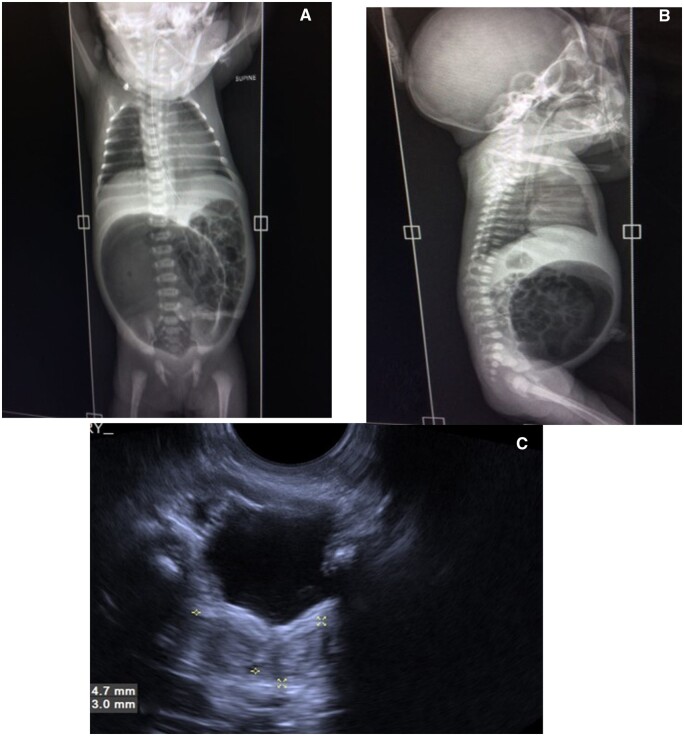

Congenital pouch colon (CPC) is highly uncommon congenital anorectal malformation where a distended pouch-like structure replaces either some part of the colon or the entire colon and communicates to the genitourinary tract through a fistula. Diagnosis of CPC is usually made after birth when neonate/infant presents with abdominal distension and absence of anal opening. Making antenatal diagnosis of CPC is difficult because of the lack of specific and verifiable signs on sonography. Hence, only a few cases of antenatal diagnosis of CPC have been reported.1,2 In our case, CPC was suspected on a routine antenatal growth scan ultrasound in the late third trimester, showing a hypoechoic tubular-shaped lesion in the pre-sacral region. With this suspicion, we suggested an institutional delivery at a tertiary level centre, and diagnosis of type III CPC was confirmed on post-delivery imaging and emergency primary surgery, done on the day 3 of life (pouch resection, division of fistula, and protective colostomy). The child also underwent further corrective surgeries in a staged manner in second year of life and recovered completely. Beforehand diagnosis prevented any unnecessary delay in operative care, reduced postoperative complications, and improved the overall outcome of this otherwise complex condition.